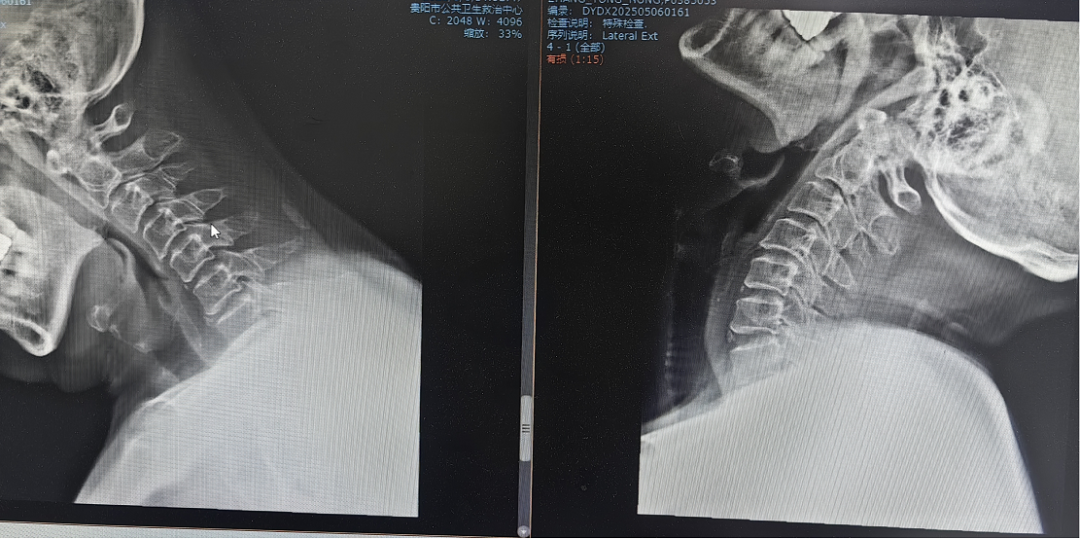

患者因"頭痛、雙上肢麻木伴下肢乏力1月"入院,此前長期保守治療效果不佳,癥狀持續(xù)加重并出現(xiàn)行走不穩(wěn)。經(jīng)多學科聯(lián)合會診,團隊決定采用國際先進的零切跡cage融合術。手術歷時2小時,出血量僅10ml,術后患者即刻感到頸部及肢體癥狀顯著緩解,術后三天即可下床活動,微創(chuàng)切口(3—4厘米)及快速康復效果獲家屬高度贊譽。

相較于傳統(tǒng)鋼板融合術,零切跡cage融合術實現(xiàn)了技術升級。

需在頸椎前方置入較大鋼板及螺釘,手術切口相對較長,存在損傷食管、氣管等周圍組織風險,且金屬鋼板長期留存體內(nèi)可能引發(fā)異物感、相鄰節(jié)段退變加速等問題。

零切跡cage融合術:

1.采用小型化、低切跡的融合器(cage),切口僅3—4厘米,術中對軟組織剝離少,有效降低血管、神經(jīng)損傷風險;

2.其零切跡設計貼合頸椎生理曲度,減少對食管刺激,避免術后吞咽不適;

3.cage融合可促進骨組織自然生長,穩(wěn)定性佳,能更好地維持頸椎活動度,加速患者術后康復進程,縮短住院時間。